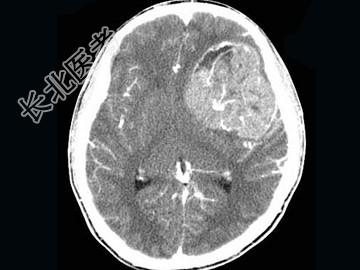

- 单项选择题男,15岁, 进行性头痛1年余,CT检查, 最可能的诊断为 ( )

A、脑膜瘤

B、脑血管畸形

C、转移瘤

D、淋巴瘤

E、胶质母细胞瘤